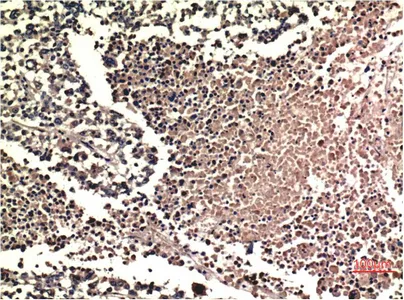

HP-1γ(3B9)Mouse Monoclonal Antibody

Cat: AMM12189

Size1:50μl Price1:$118

Size2:100μl Price2:$220

Size3:500μl Price3:$980

Size2:100μl Price2:$220

Size3:500μl Price3:$980